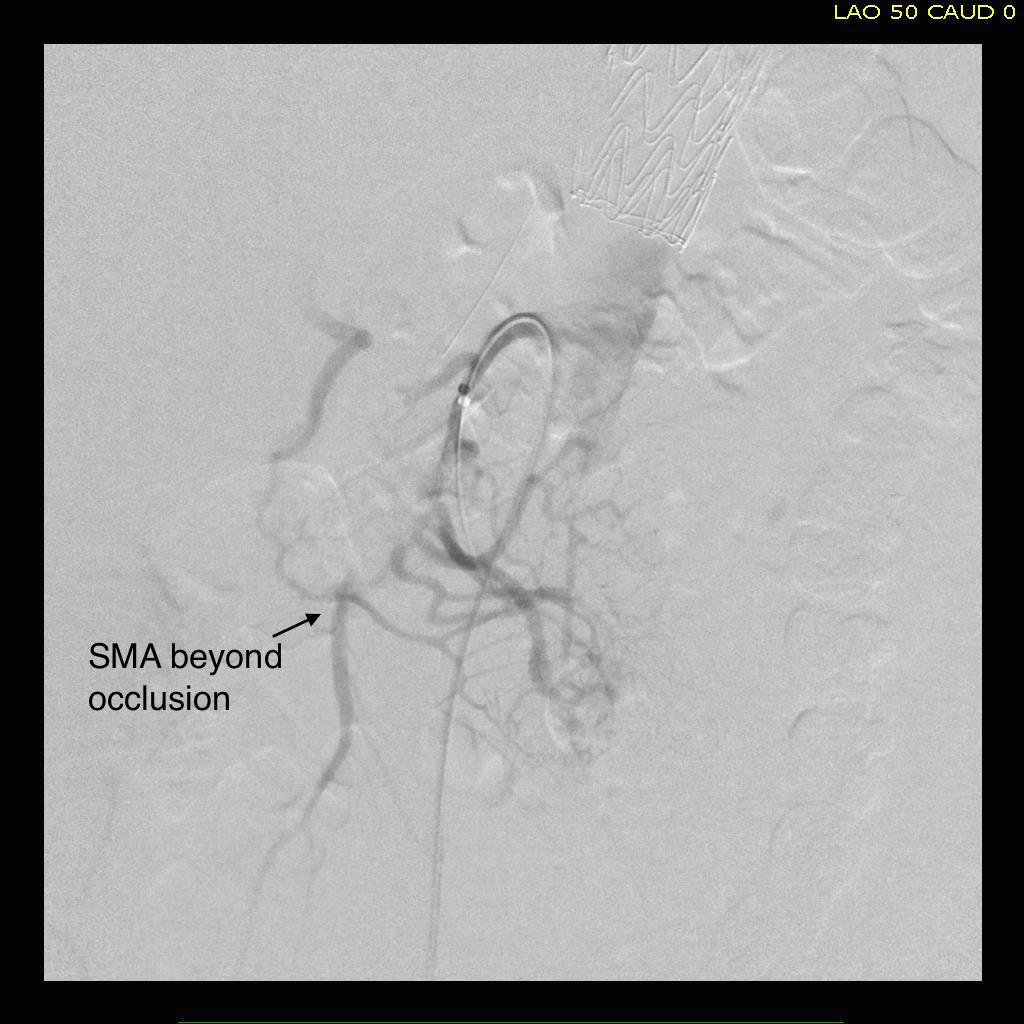

The patient is a middle aged man with risk factors of NIDDM and prior history of DVT who developed severe mid-abdominal pain at 5pm. He came to the ED at around 11pm and had a general surgery consultation who ordered a CT Angiogram showing SMA occlusion (pictured below).

Heparin was started, and at 11:30, vascular surgery was consulted. The patient had a soft, doughy texture to his abdomen, but great pain with palpation -classic pain out of proportion to the exam. Determining the patient to have acute mesenteric ischemia from a thromboembolism, I took the patient to our hybrid angiographic OR suite with the plan for arteriography, possible open thrombectomy, and exploratory laparotomy.

Arteriography from femoral access showed an occlusion of the SMA beyond the middle colic artery, a typical pattern for an embolism that occurs when embolism lodges distally and propogates proximally (image below).

I got Glidewire access into the ileocolic terminus of the SMA, exchanged for a Rosen wire, over which I placed an 8F sheath into the proximal SMA. This was a rather large sheath meant to catch thrombus as I suctioned it out with a 6F Penumbra catheter. This is another technique I borrowed from the neurointerventionalists. Whenever a stroke alert is going on, curiosity drives me to peak in and see what marvelous gadget or gewgaw they are using, and I was impressed by how efficiently the neurointerventionalists were able to get to the smallest thrombus in the furthest branch vessels. I was prepped for open thrombectomy, consented for bypass if necessary, but having experience in suctioning clot through single catheters and sheaths, I thought the simple design of the Penumbra and its efficacy in the cerebral system could easily translate into the mesenteric.The problem with open thrombectomy is the inability to see if you have cleared thrombus from all the branches unless you do an arteriogram after you’ve completed your procedure. This may be a significant contributor to the 20-30% bowel resection rate that occurs on second look laparotomy in my old paper and in the literature since its publication.

The Penumbra was effective in removing much of the fresh thrombus, but I was also cognizant of the fact that pulling out the catheter will draw clot into the 8F sheath that did not make it into the catheter. I placed a wire, and removed the sheath to expel much of the bulky thrombus (picture below).